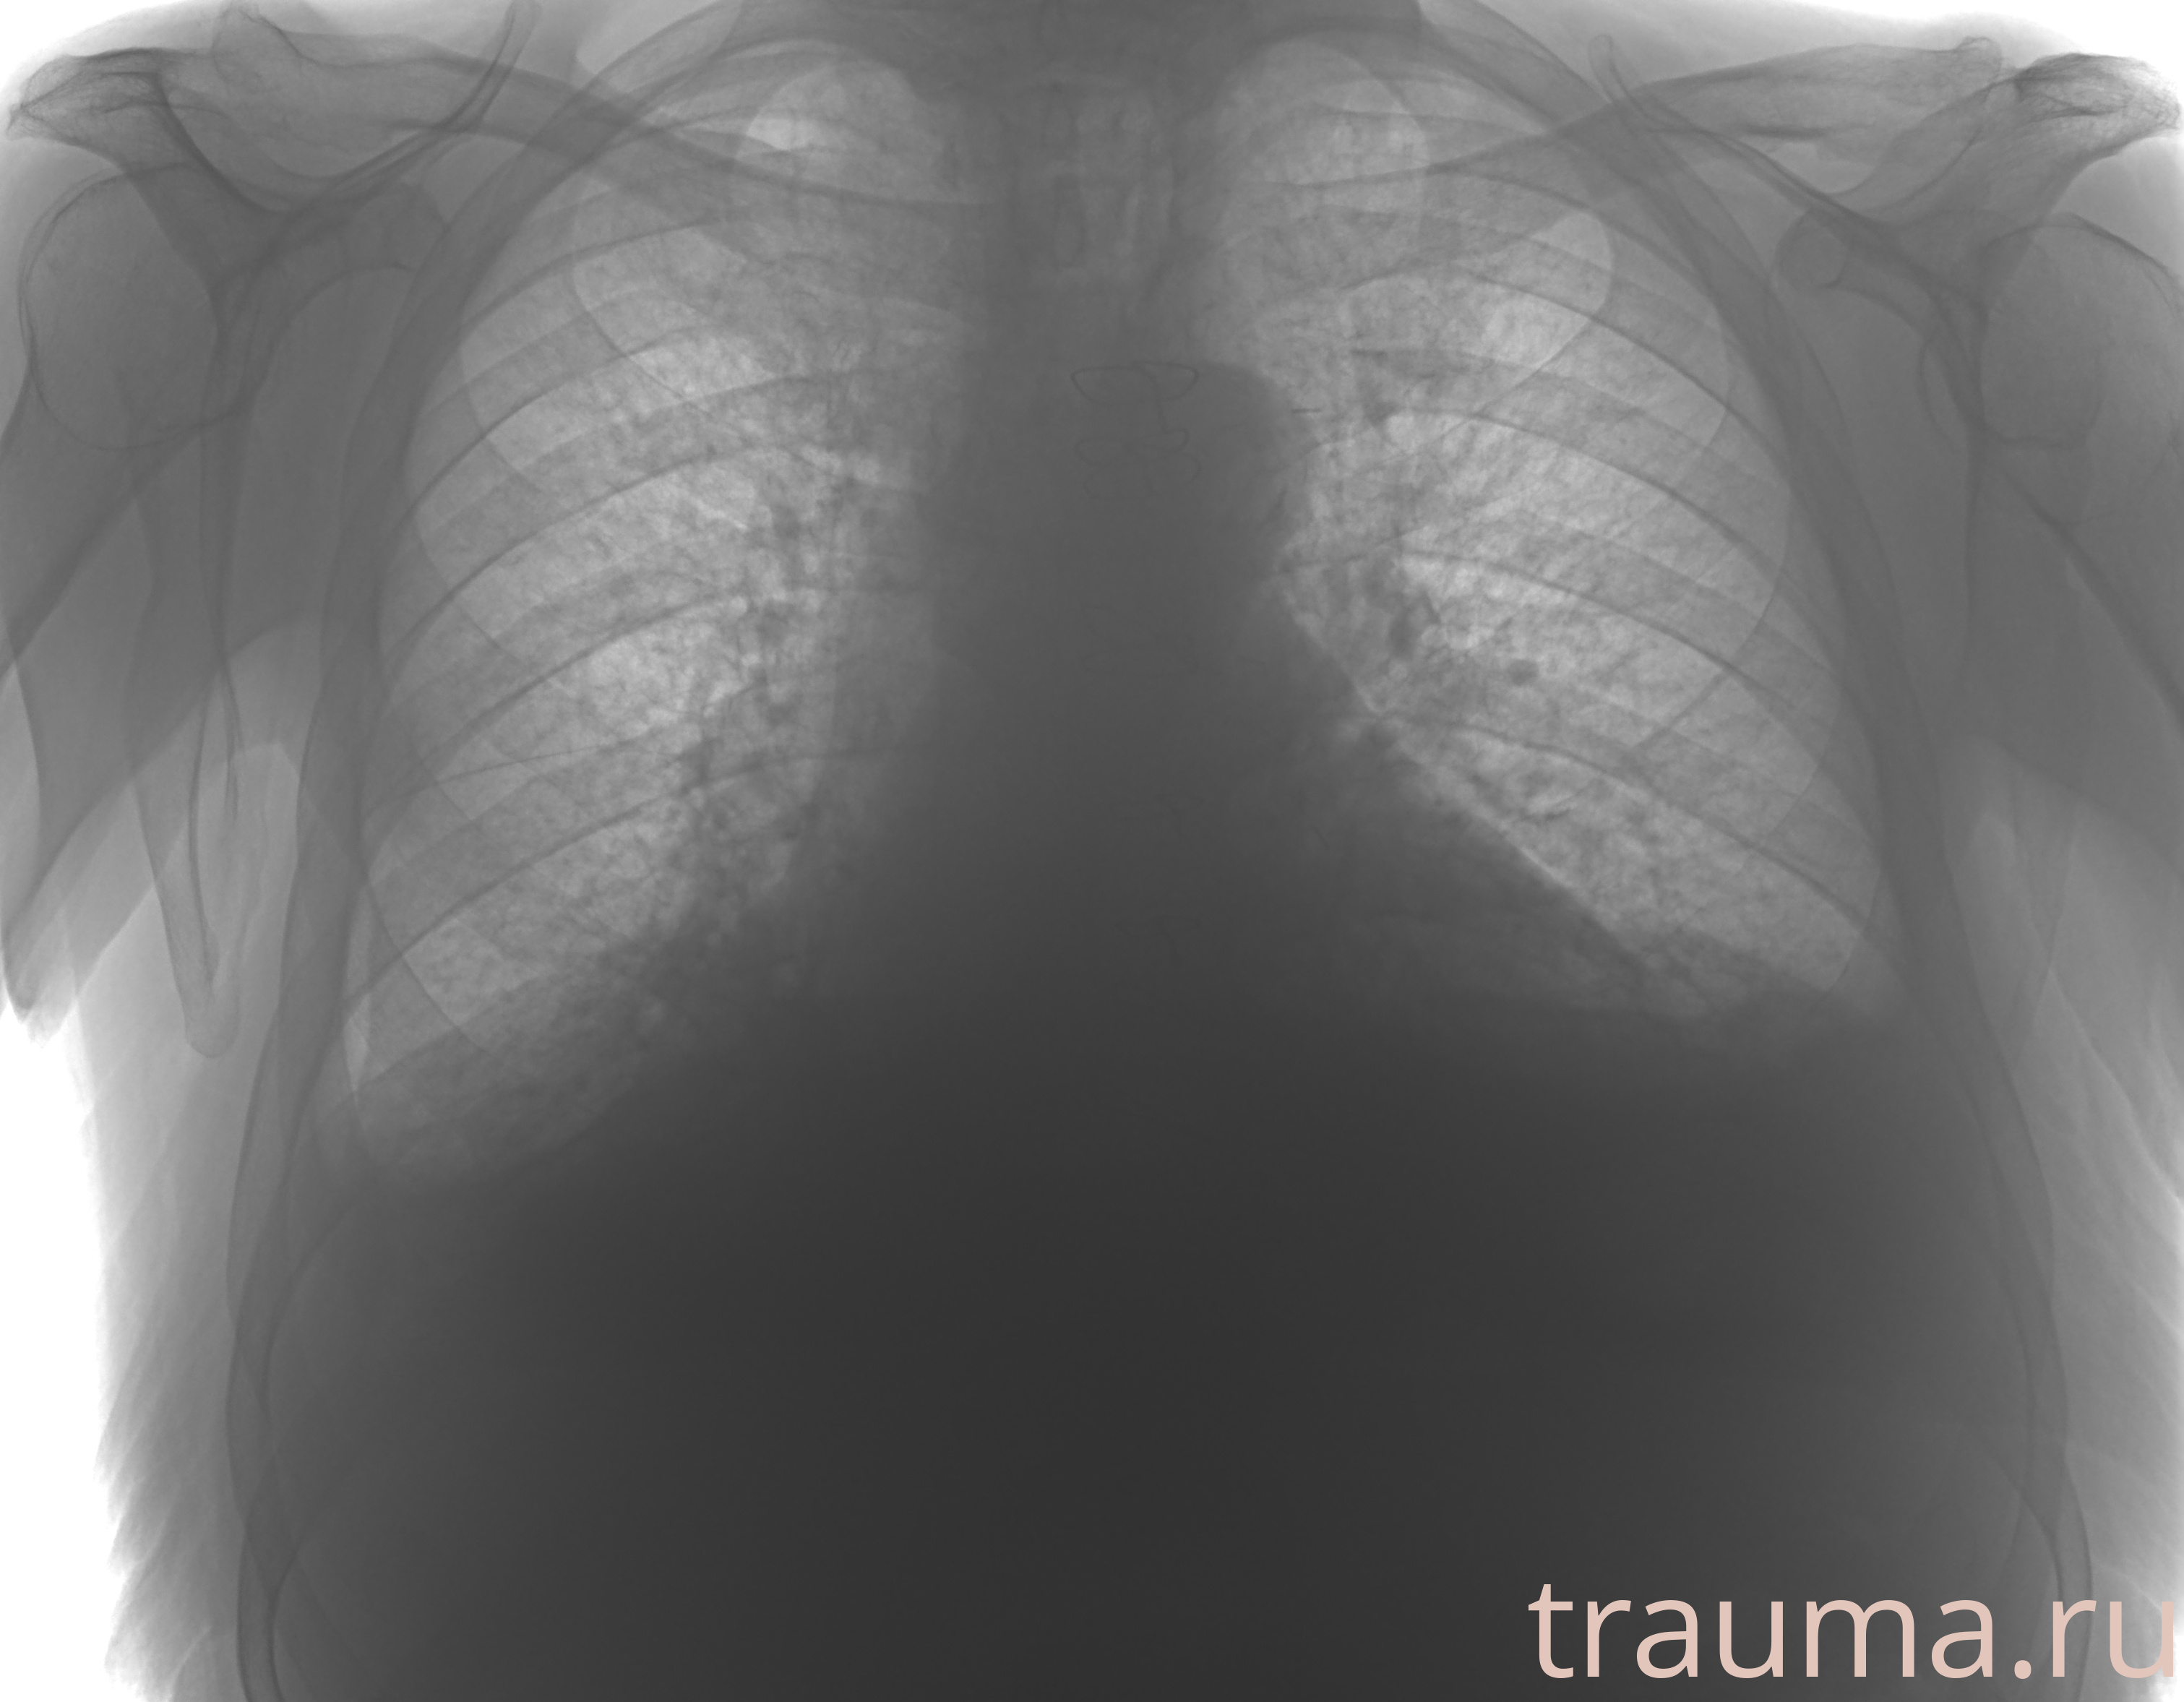

Рентген на дому: по вашему адресу приезжает врач-рентгенолог, травматолог-ортопед с мобильным рентгеновским аппаратом, проводит диагностику травмы или заболевания, делает необходимые рентгенограммы, дает рекомендации по дальнейшему лечению. Получить качественные снимки в домашних условиях возможно благодаря уникальной методике, разработанной МосРентген Центром для института  Склифосовского

при переломе шейки бедра и пневмонии от компании МосРентген Центр - партнера Института имени Склифосовского